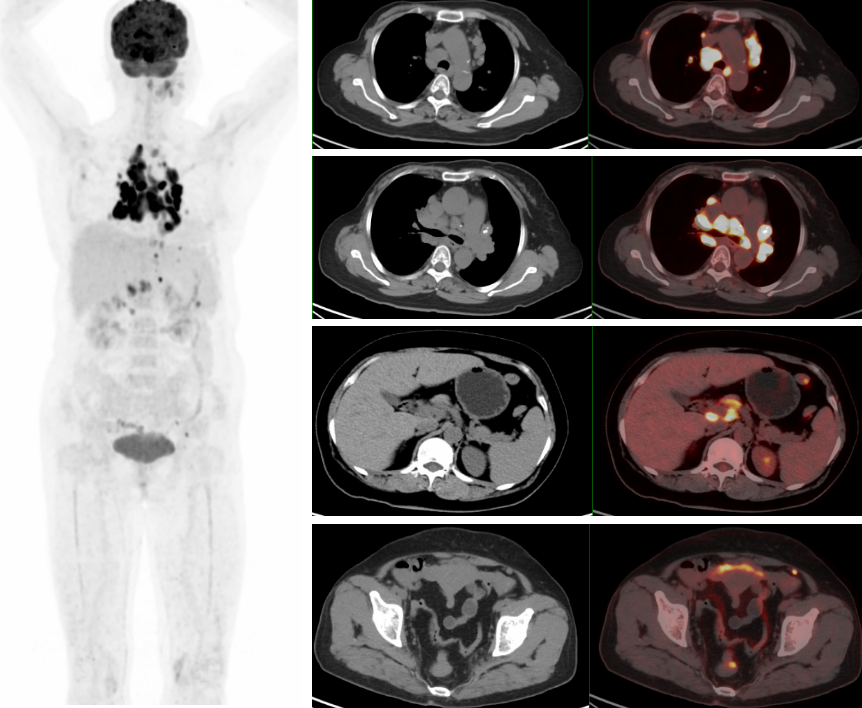

PET/CT示:雙側鎖骨上、縱隔、胸骨后、雙肺門、雙側肋骨旁、腹腔、腹膜后、盆腔及左側腹股溝見多枚代謝異常增高淋巴結,較大者約3.4×2.1cm,SUVmax約20.7。

PET/CT診斷:考慮結節病,建議病理檢查。

18F-FDG PET/CT在腫瘤患者的全身評估中具有顯著優勢,在乳腺癌術后出現縱隔和肺門腫大淋巴結時,不但能顯示淋巴結全身的分布特征,且能更早發現胸外病變及隱匿性病變,同時體現不同部位淋巴結的FDG攝取程度,判定病灶活動性,有利于結節病與乳腺癌術后復發或淋巴瘤等的鑒別診斷。由于結節病的診斷主要依靠組織病理學活檢,PET/CT可以提示適合的活檢部位,提高活檢診斷成功率。

此例患者由于乳腺癌的病史,臨床初步懷疑轉移。PET/CT顯示縱隔、肺門淋巴結腫大,且呈對稱性分布,密度均勻,邊界清晰,無明顯融合,FDG高攝取;此外可見多發腹盆部,頸部淋巴結次之,分布較散,體積及FDG攝取小于縱隔和肺門淋巴結,也不是乳腺癌術后易轉移的部位。綜上考慮符合結節病表現,最終得到病理證實,患者因此避免了不必要的抗腫瘤治療。